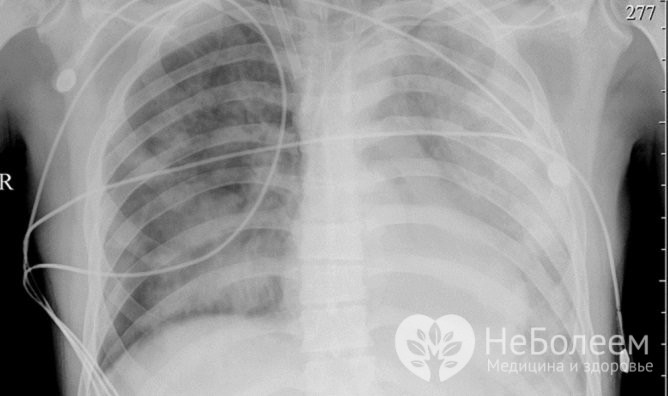

Серьезным осложнением аденовирусной инфекции является развитие аденовирусной пневмонии, что можно увидеть на рентгенограмме.